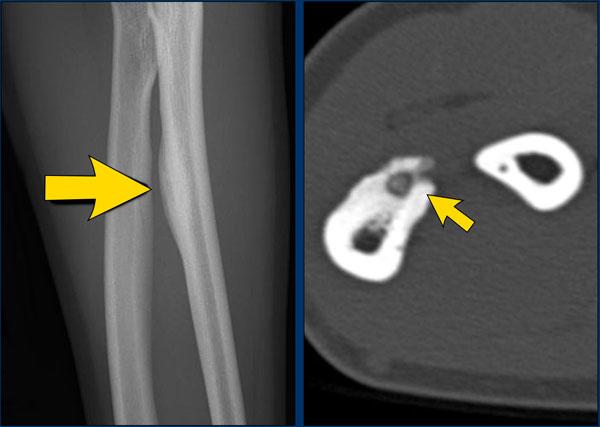

Hình ảnh

Phản ứng màng xương lành tính trong u xương dạng xương.

Mũi tên lớn chỉ phản ứng màng xương đặc.

Mũi tên nhỏ chỉ ổ tổn thương trung tâm.

Images

- Osteosarcoma

Irregular cortical destruction - Sarcôm Ewing

Phá hủy vỏ xương (mũi tên xanh) và phản ứng màng xương xâm lấn (đầu mũi tên).